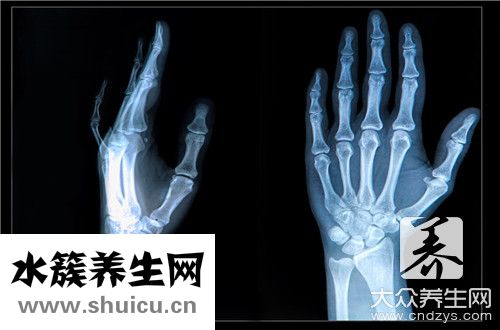

在臨床醫學上,假如骨折愈合圓滿得話,大概一個半月上下,應當就會有顯著的骨痂生長發育,徹底的骨折愈合,大概需要三個月上下的時間,所以說假如骨折愈合圓滿得話,針對折股骨折徹底的痊愈,大概需要三個月上下的時間。

可是實際三個月上下骨折愈合是否,最關鍵的還是需要依據,復診的影片來明確的,由于臨床醫學上,終究影響骨折愈合要素還是十分多的,例如患者年紀的尺寸,患者的體質,那時候損害的比較嚴重水平,及其后需積極主動醫治維護的水平,都是立即影響骨折愈合過程的,所以說最關鍵的,還是需要依據復診的影片來決策的。

假如拍片子查驗,骨折處骨折線早已徹底的模糊不清看不出了,那么就證實骨折的地區早已徹底的痊愈,相反我覺得還是需要注意休息維護一段時間的。